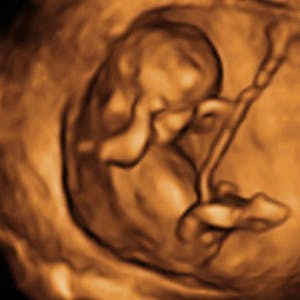

Gravid

Vi gør en dyd ud af at klæde dig godt på både før, under og efter din graviditet. Vi ved, at der kan komme mange spørgsmål til din graviditet, fødsel, amning, din babys udvikling og mange flere emner, derfor har vi samlet guides, tips & tricks samt læsernes egne fortællinger i dette gravid univers.